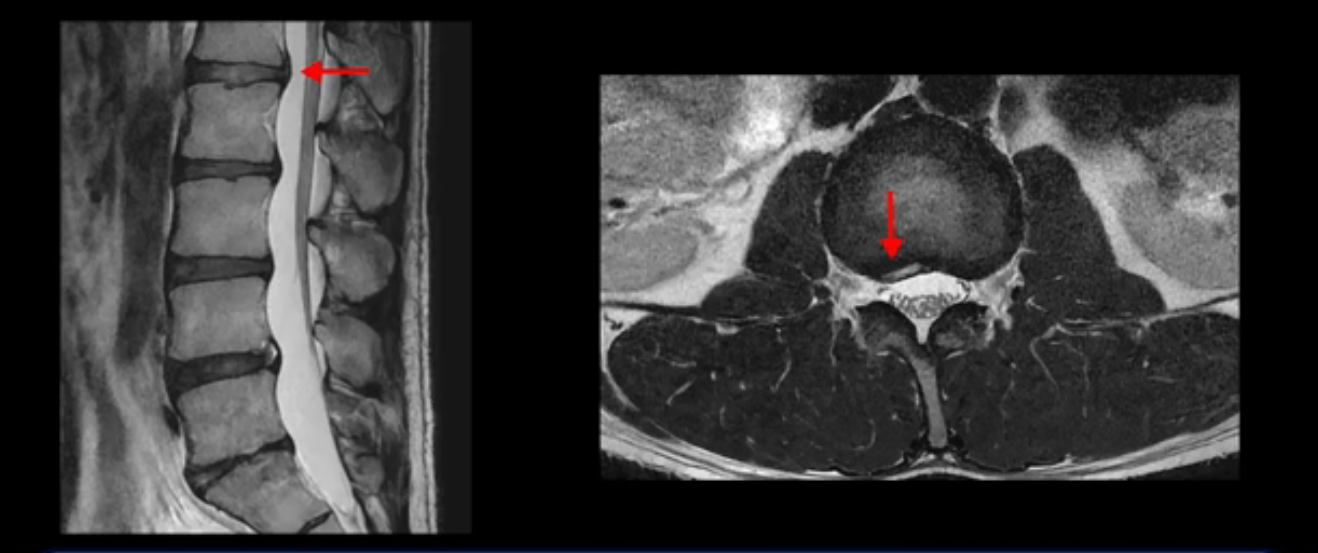

그런데 이분의 증상과 MRI가 전혀 일치하지 않는데, 왜 그런지 지금부터 자세히 설명드립니다. 이분 증상은 앉으면 엉치와 허리가 심하게 아파 10분 이상 앉는 게 어렵고 양쪽 발가락이 앉아있을 때나 누워있을 때 다 저립니다. 걸을 때도 아파서 10분 걷기도 어렵습니다. MRI를 마디마디 살펴보면 1번 2번은 오른쪽으로 살짝 밀려나온 디스크가 있지만 전혀 심하지 않고, 뒤에 또 설명하겠지만 최근에 밀려나온 급성 디스크가 아니고 오래된 디스크로 판단됩니다.

2번 3번도 비교적 디스크 상태는 좋고 신경 구멍 넓이도 아주 넓습니다.

5번 1번 역시 가운데로 디스크 조금 밀려 나와있지만 신경 공간 넓이는 아주 넓어서 신경 눌림 있을 거라고 예상이 안됩니다.

추간공도 보시다시피 왼쪽, 오른쪽 전부 다 매우 넓어서 신경이 눌릴만한 부분이 전혀 보이지 않습니다.